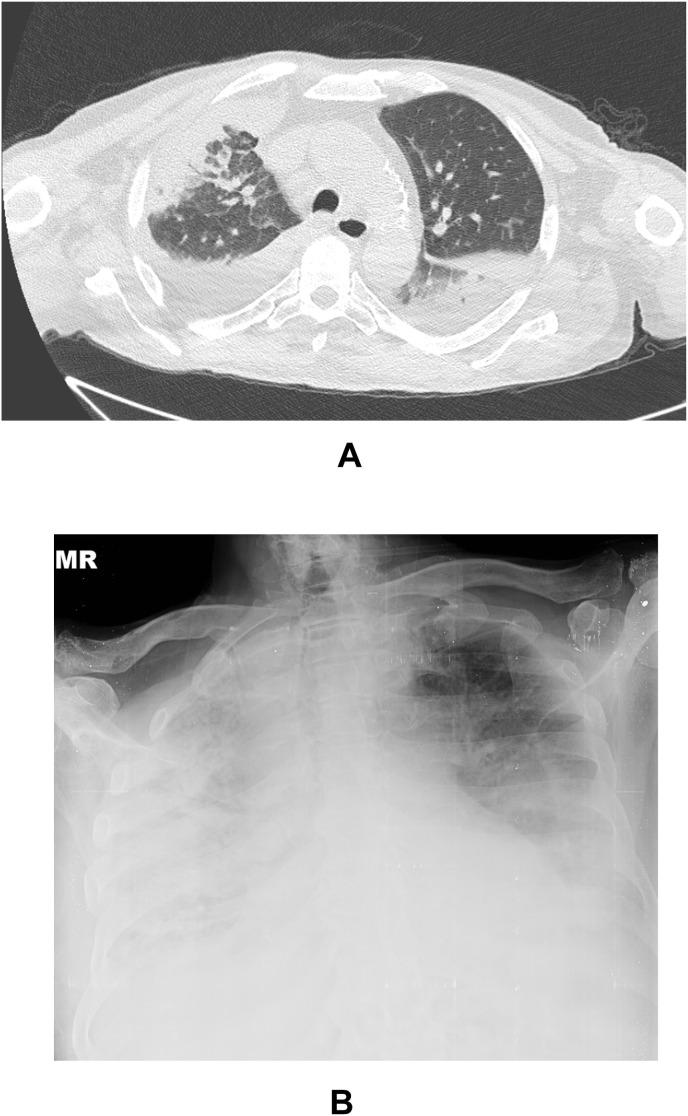

A total of 19 febrile neutropenic patients were analyzed. A male predominance was noted. Eleven cases had hematological malignancies. Fourteen of the cases were previously received chemotherapy. Five patients had severe neutropenia: 3 had hematologic cancer and none died. 17 (89.5%) cases have pulmonary involvement and seven of them had severe disease with acute respiratory distress syndrome (ARDS). Three cases with ARDS were died. 12 of them received G-CSF for treatment. Five cases were developed respiratory failure after G-CSF use. Overall mortality was 15.8%, while death was not observed in patients without malignancy and solid organ tumors, the mortality rate was 27% in cases with hematological malignancies.

共分析了 19 例发热性中性粒细胞减少症患者。男性居多。11 例有血液系统恶性肿瘤。14 例以前接受过化疗。5 例有严重中性粒细胞减少症:3 例患有血液系统癌症,无死亡病例。17 例(89.5%)有肺部受累,其中 7 例有严重疾病,包括急性呼吸窘迫综合征(ARDS)。3 例 ARDS 患者死亡。其中 12 例接受 G-CSF 治疗。5 例在使用 G-CSF 后发生呼吸衰竭。总死亡率为 15.8%,而无恶性肿瘤和实体器官肿瘤的患者未观察到死亡,血液系统恶性肿瘤患者的死亡率为 27%。